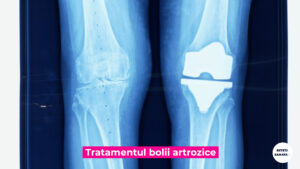

Diagnosticul acestei afectiuni se face pe baza unui examen clinic efectuat de ortoped si al unor radiografii ale articulatiei. Boala artrozica poate aparea la nivelul oricarei articulatii, in special la nivelul soldului, genunchiului, sau a umarului – avand denumirile specifice de coxartroza, gonartroza, sau omartroza.

Cand tratamentul simptomatic nu mai da rezultate, se apeleaza la chirurgie. Diagnosticul acestei afectiuni se face pe baza unui examen clinic efectuat de ortoped si a unor radiografii ale articulatiei. Factorii de risc ai bolii artrozice sunt: traumele articulare, suprasolicitarile articulare, in cazul fostilor sportivi de performanta, varsta si obezitatea.